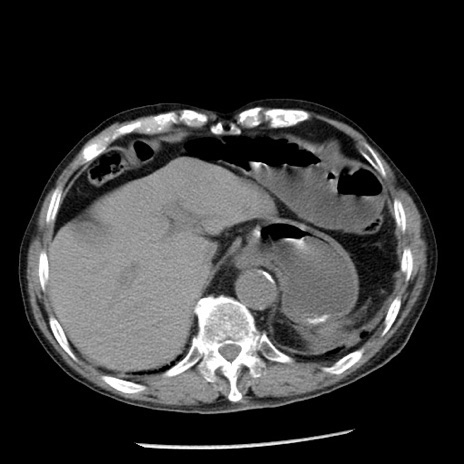

症例26(横断像)

【症例】80歳代男性

【主訴】嘔吐

【現病歴】昨晩2回嘔吐あり、今朝になっても嘔吐あり。来院。

【既往歴】胃潰瘍

【身体所見】意識清明、BT 37.6℃、BP 166/95mmHg、HR 100bpm、SpO2 97%、腹部:平坦・軟、腸蠕動音聴取良好、圧痛なし。

【データ】WBC 21900、CRP 1.46